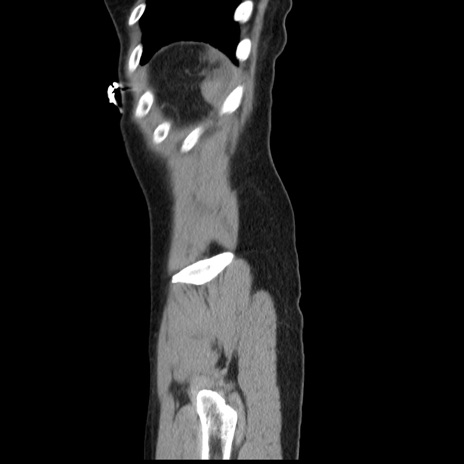

症例10(矢状断像)

【症例】 50歳代女性

【主訴】 腹痛

【現病歴】前日生レバーを食べた。今朝に排便あり。 昼前に突然発症の腹痛を生じ、当院救急外来を受診した。

【既往歴】 子宮筋腫にてで子宮全摘後

【身体所見】 意識清明、腹部:平坦、軟、下腹部やや左を中心に圧痛・反跳痛あり、筋性防御あり

【データ】WBC 7800、CRP 0.07